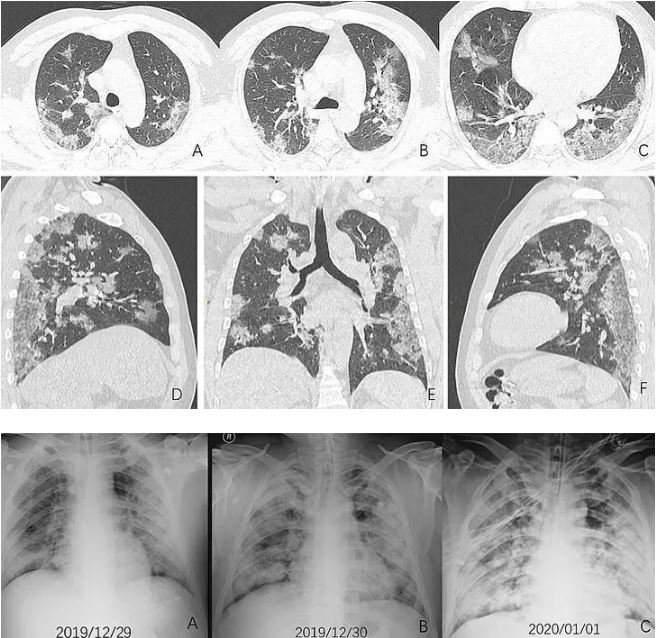

Kuzey Amerika Radyoloji Derneği (RSNA), virüs ile ilgili yapılan araştırmalar kapsamında Covid-19 hastalarının akciğerlerinin tomografi ve röntgen görüntülerini yayınladı. Euronews'te yer alan habere göre, koronavirüsün kaynağı olduğu düşünülen Vuhan kentindeki balık pazarında ulaşım görevlisi olan 44 yaşındaki bir erkeğin röntgen (X-ray) görüntülerindeki "opasifikasyon (buzlu cam görünümleri)" denilen beyaz lekeler, hastada oluşan zatürrenin boyutunu resmediyor.

BİR HAFTA SONRA ÖLDÜ

Akut solunum sıkıntısı sendromu ve ileri derece zatürre teşhisi konulan hasta, 13 gün süren yüksek ateş ve öksürük şikayeti üzerine hastaneye başvurduktan bir hafta sonra hayatını kaybetti. Söz konusu hasta şüpheli Covid-19 vakası olarak tanımlanıyordu.